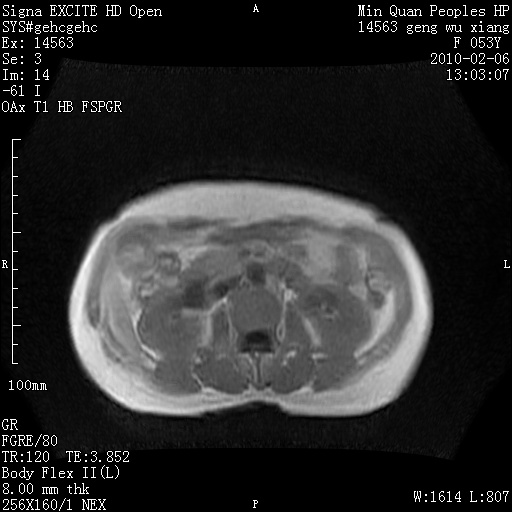

标题: MRI2762:胆道梗阻原因?

f,53y,全身黄染多日。

高位胆道梗阻 胆管癌可能性大

支持 高位胆道梗阻 胆管癌可能性大。